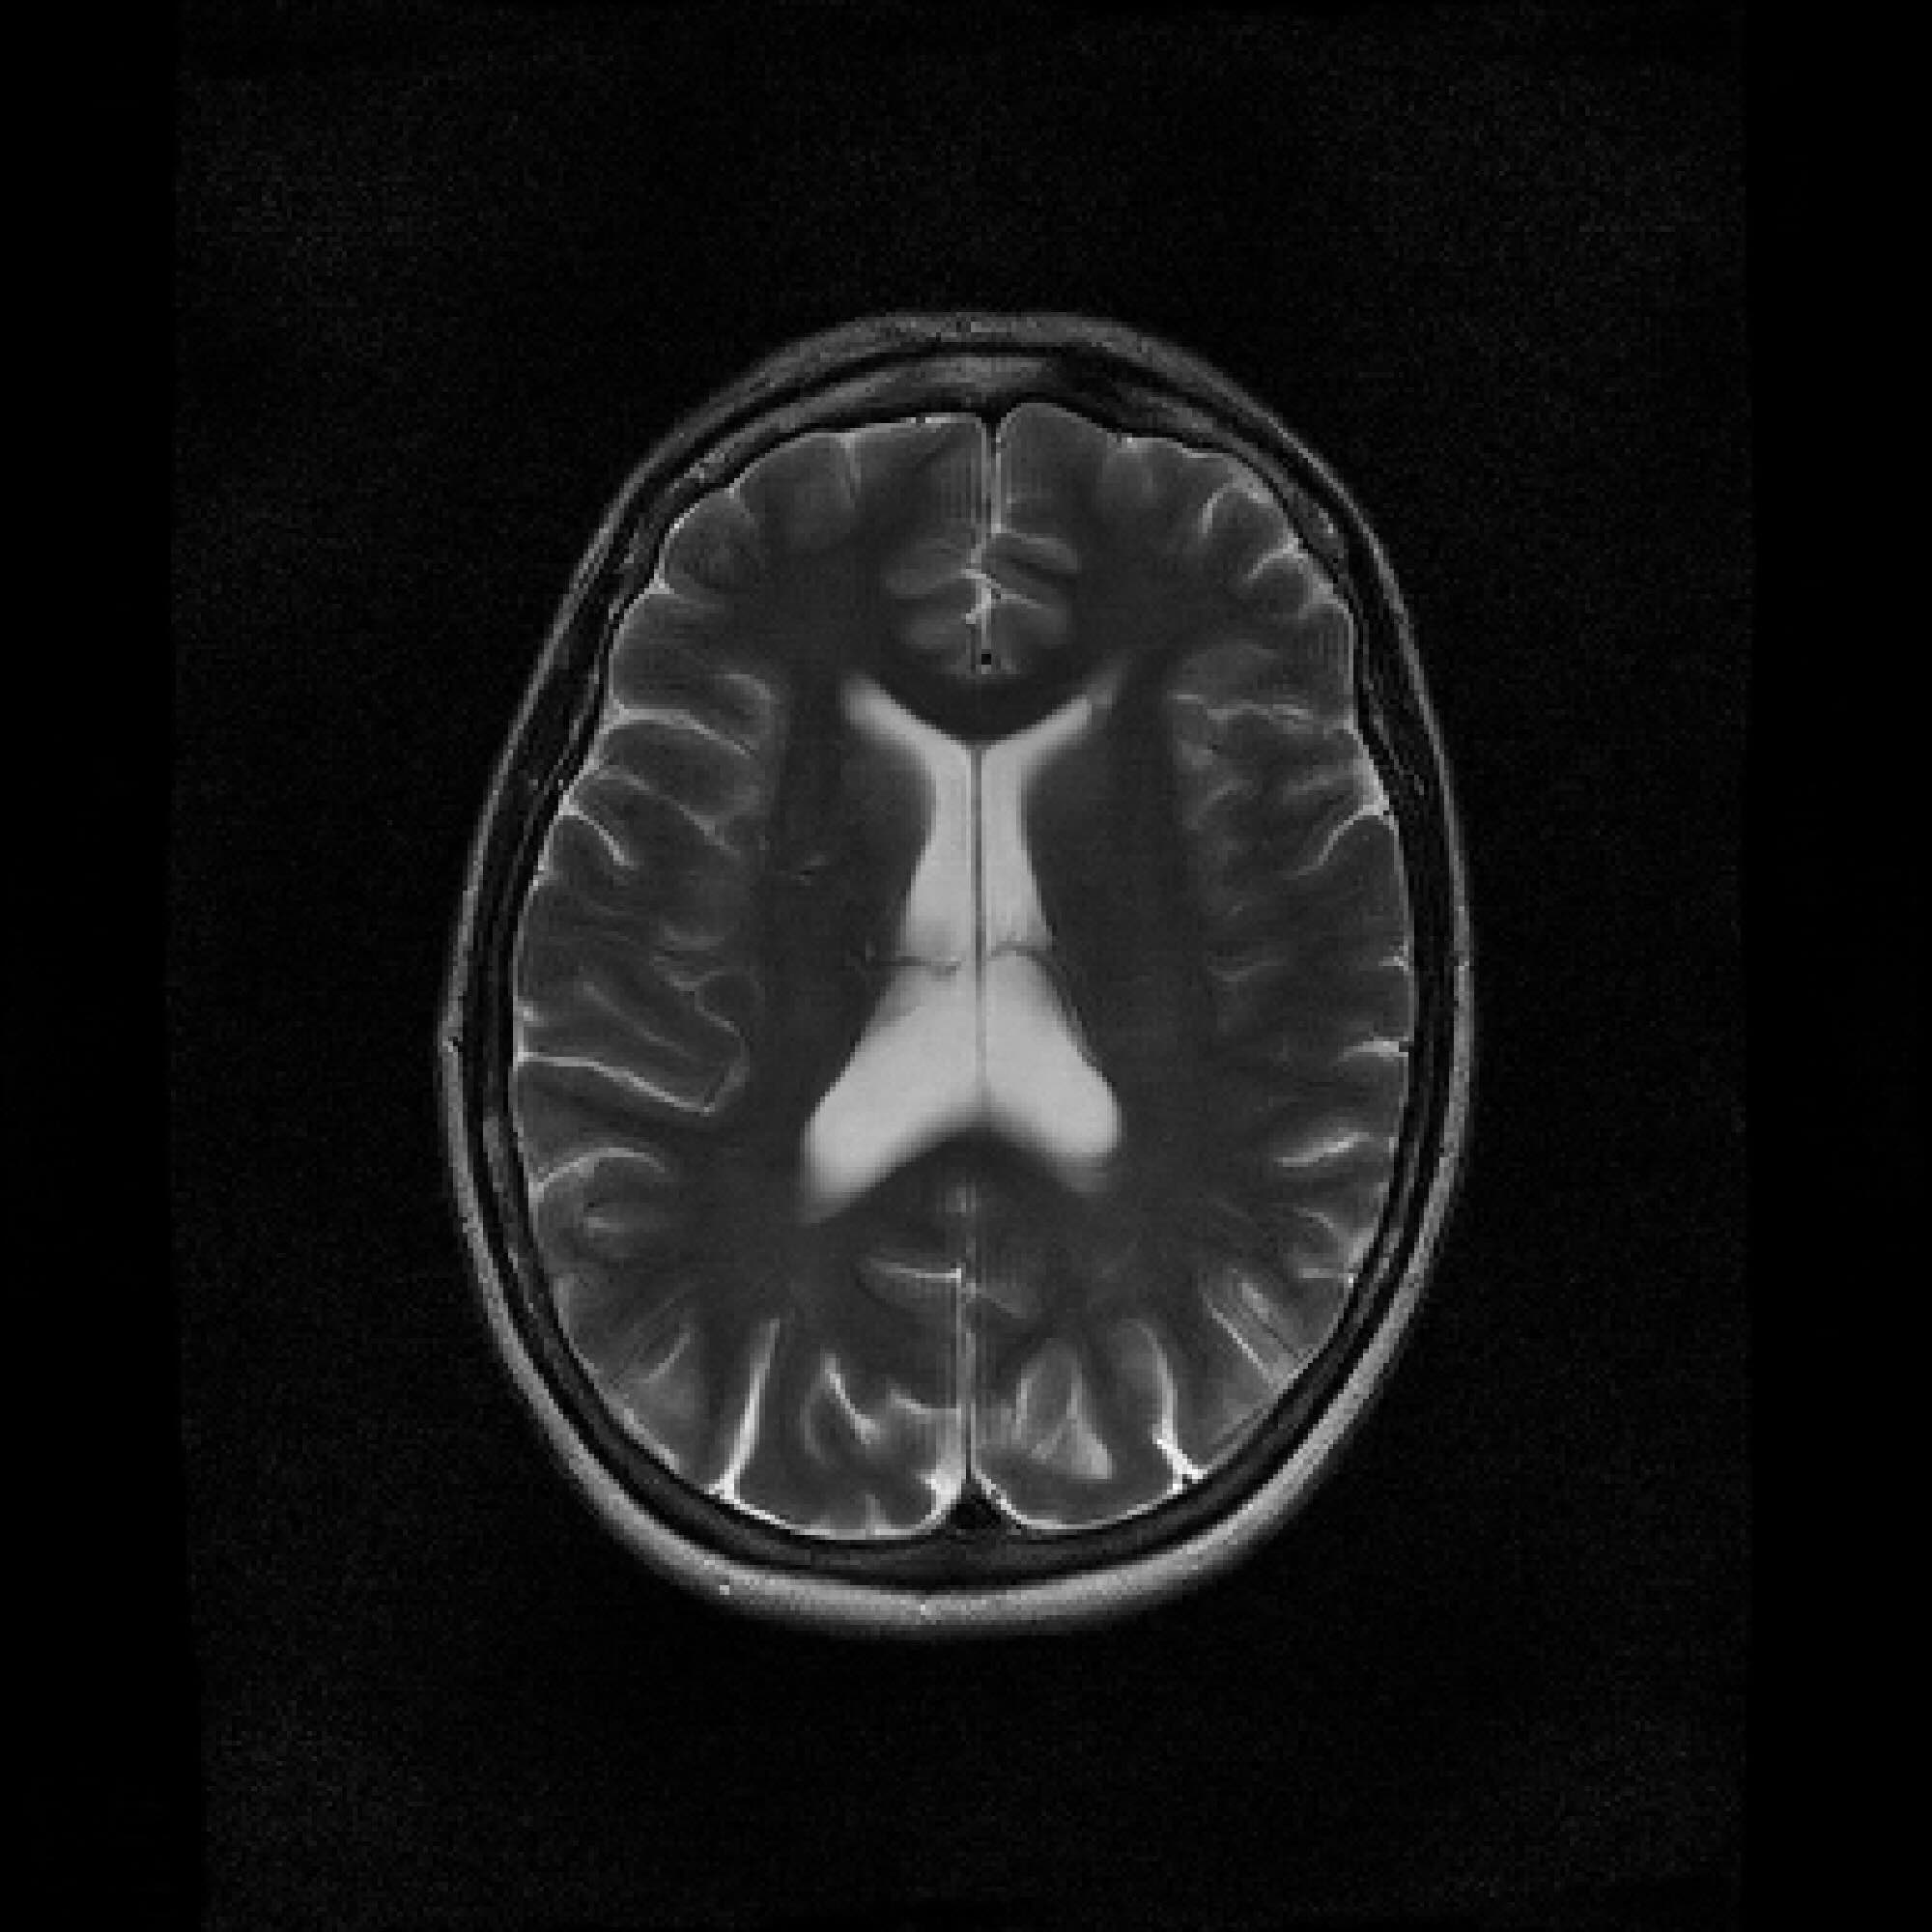

Figure 2: Example MRI magnitude reconstructions with S=25S=25 training slices at acceleration factor R=7R=7. PaDIS-MRI reconstructions are sharper and more faithful to the fully-sampled ground truth. Insets are shown to highlight detail.

Figure 2 provides a visual comparison of the reconstruction quality of each method on example slices. In reconstructions from the S=25,R=7S=25,R=7 models, FastMRI-EDM exhibits slightly more blurring and loss of fine structural details, particularly in regions with complex anatomical features. PaDIS-MRI, in contrast, preserves sharper boundaries and finer details. This enhanced data efficiency can be attributed to the patch-based prior’s ability to learn localized structural motifs more effectively from limited examples. Figure 6 in the Appendix shows similar reconstructions at S=200,R=7S=200,R=7 where FastMRI-EDM more closely approaches the performance of PaDIS-MRI but still struggles with highly detailed anatomy. At both dataset sizes, MoDL underperforms the diffusion priors. In Figure 2, MoDL’s FLAIR reconstruction exhibits pronounced artifacts, likely reflecting reduced generalizability of a supervised prior when the training distribution underrepresents FLAIR.

T2-Axial T2-Axial T2-Axial FLAIR T1

Figure 6: Dataset Size S=200S=200, Undersampling Rate R=7R=7 Inset Comparisons. The top row shows the ground truth images. The middle row shows the FastMRI-EDM reconstructions. The bottom row shows the PaDIS-MRI reconstructions, which exhibit slight perceptual improvements at the insets.